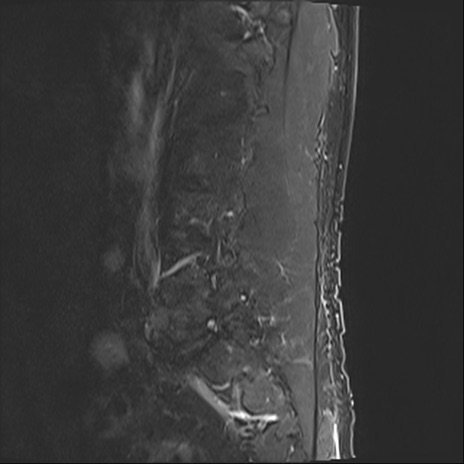

【整形】TIPS症例2 腰椎MRI STIR(矢状断像)

【症例】70歳代男性

【主訴】左下肢痛

【現病歴】2週間前くらいから腰痛、左下肢痛あり。左臀部から大腿、下腿外側のしびれが常時ある。歩行とともに同部位の痛みあり。

【身体所見】Lasegue70-/60+、Bragard-/±、PTR ±/±、ATR -/-、IP 5/5、TA 5/4、TS 5/5、EHL 右第1足趾なし/3、FHL 5/5、hypersthesia(-)、足背動脈触知良好

異常所見と診断は?